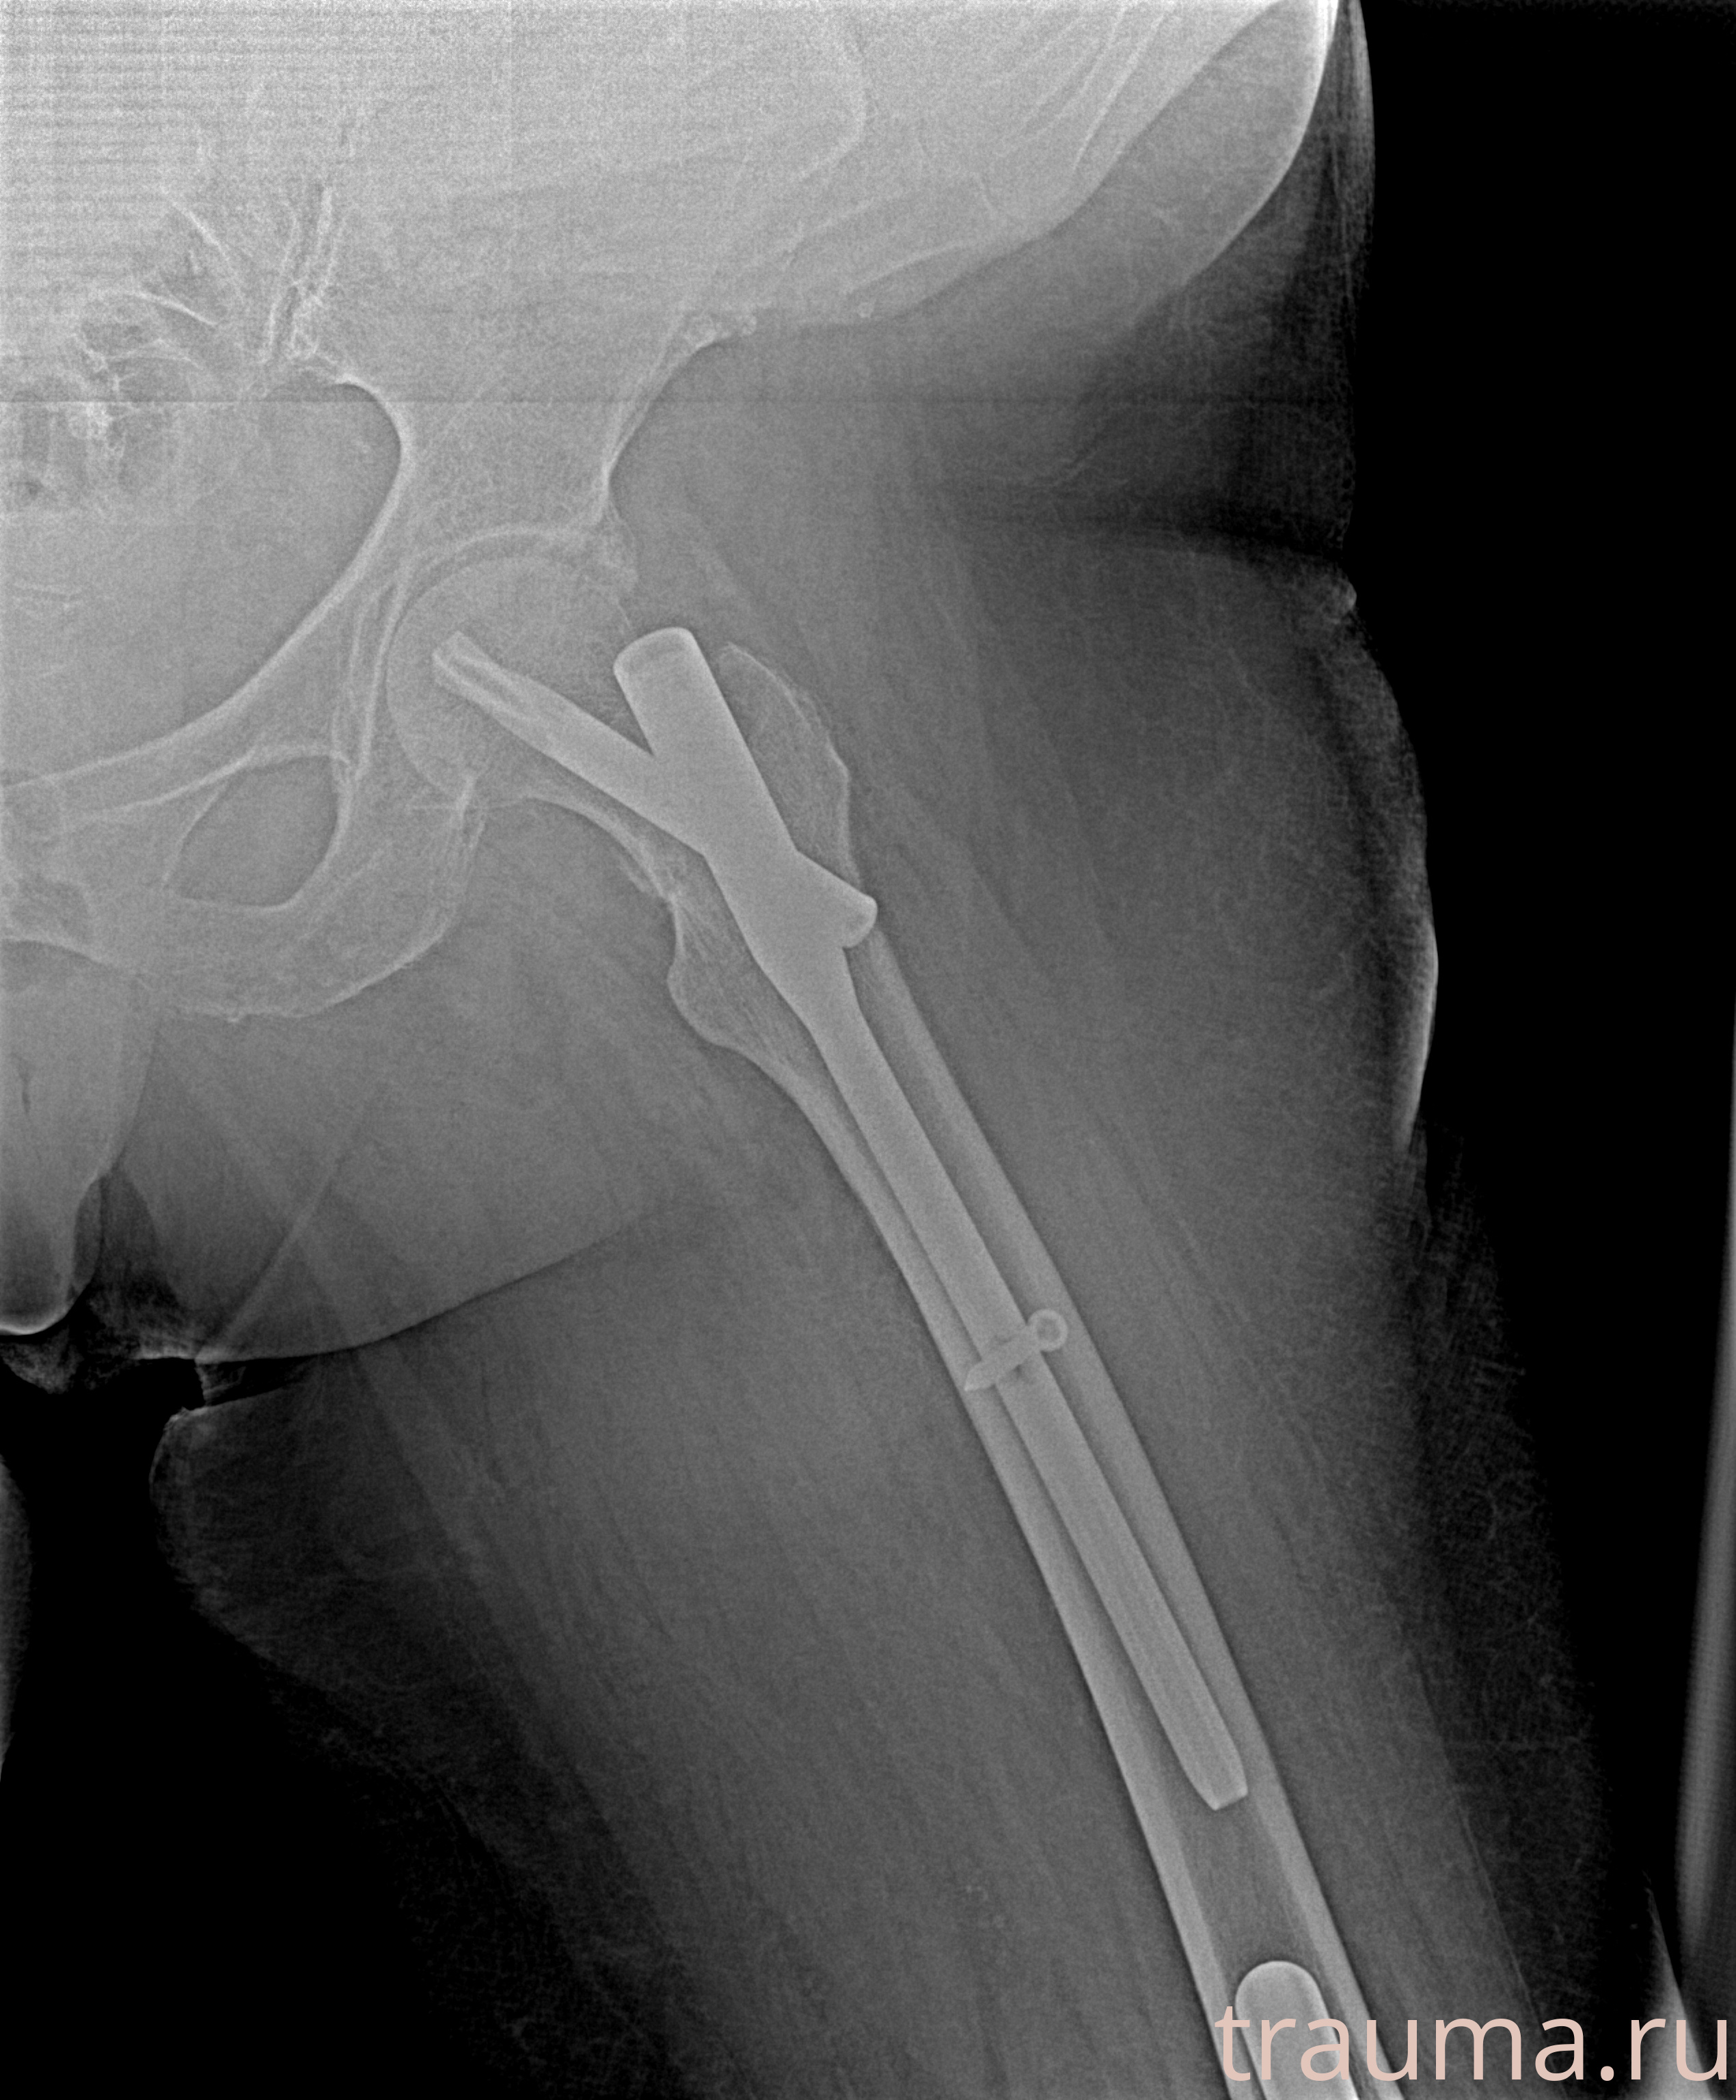

Рентгенограммы

Рентген на дому: по вашему адресу приезжает врач-рентгенолог, травматолог-ортопед с мобильным рентгеновским аппаратом, проводит диагностику травмы или заболевания, делает необходимые рентгенограммы, дает рекомендации по дальнейшему лечению. Получить качественные снимки в домашних условиях возможно благодаря уникальной методике, разработанной МосРентген Центром для института  Склифосовского